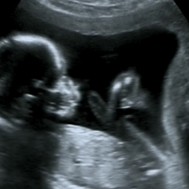

Baby: Week 16

You are 12cm long and weigh about 190g. Your chest moves up and down and blood vessels are visible through your skin.

Your mother gets a peek at you for the first time this week, with an ultrasound exam to assess your growth and development, gestational age, and to detect problems that need attention. Mum can see your movements—kicking, flexing, thumb sucking, and perhaps can tell what sex you are![1]